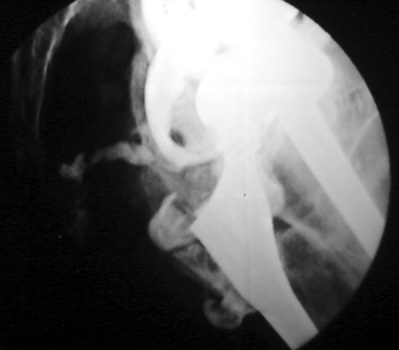

Aspiration of hip after removal of prosthesis. Needle placed

at femoral edge where fluid collects. Needle should not be placed in acetabular

area, which may not be fully intact, risking needle entry into pelvic cavity.